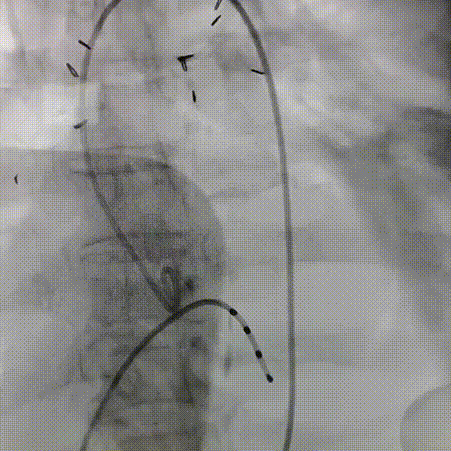

球囊预扩

过弓跨瓣